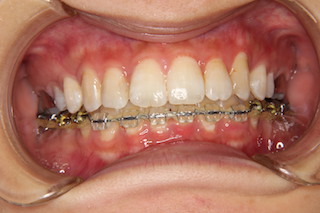

正面・・随分綺麗になって来ました!

上顎・・見えない位置のインプラントで奥歯を更に奥へと動かします